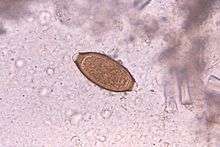

Helminthic therapy

In an experimental idea called helminthic therapy, moderate hookworm infections have been demonstrated to have beneficial effects on hosts suffering from diseases linked to overactive immune systems. This is possibly explained by the hygiene hypothesis.[32] Hookworm therapy is currently in the trial stage at the University of Nottingham. Due to the unconventional nature of this therapy, it is not widely used.

- Trichuris suis is a pig whipworm that been shown in one study to improve Crohn's disease symptoms.[48]